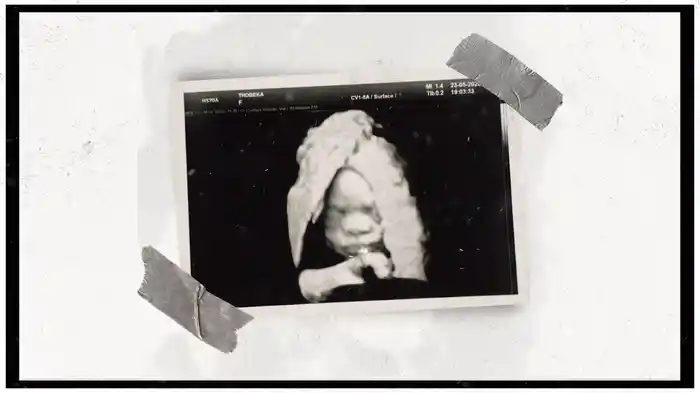

Egyptian Cotton (Visualizer)